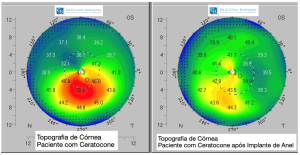

O acompanhamento constante da doença é importante, pois o Ceratocone é uma doença progressiva. Tanto o diagnóstico da doença como a verificação de sua progressão dependem de exames especiais, destacando-se a topografia da córnea (estudo da superfície), tomografia de córnea (estudo 3D), acuidade visual e refração (avaliação da óptica ocular).

Topografia Corneana ou Tomografia de Córnea – São exames capazes de avaliar as diversas curvaturas da Córnea. É um excelente instrumento para confirmar o diagnóstico de Ceratocone, mesmo quando os sinais característicos ainda não são observados. A localização do ápice e a progressão da doença podem ser visualizadas facilmente quando se analisam os mapas coloridos, o que permite classificar a doença.

A indicação do Crosslink é quando ocorre piora e evolução do Ceratocone, documentado no exame de Topografia de Córnea e piora visual.

O objetivo do anel é regularizar e diminuir a curvatura corneana, e consequentemente melhorar a visão. Além disso, esse dispositivo é capaz de diminuir ou corrigir os erros de refração da Córnea de um paciente com Ceratocone.